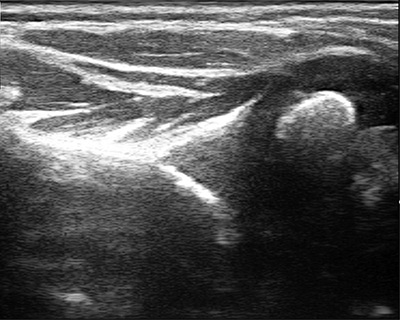

If the shoulder is left untreated, it can deform as it grows, a condition known as glenohumeral dysplasia (Figure 3a). Glenohumeral dysplasia can get worse with age but can be severe even in children as young as three months old. Some children may dislocate the shoulder joint completely.

Figure 3a: Severe glenohumeral dysplasia on ultrasound

Many patients come to us too late to implement the teapot splint, and shoulder tightness with internal rotation has already set in. In children less than a year of age, it may be possible to stretch out the shoulder using botulinum toxin to temporarily weaken the muscles that turn the shoulder in, and then to cast the shoulder in a position of external rotation (Figure 4). This has to be done with the child asleep and so requires general anesthesia. Ultrasound is used to confirm that the joint is in place after the shoulder is stretched, and is it also used intermittently after the cast is removed to make sure that the shoulder is growing and developing well. A teapot splint may be used after casting for up to two years during sleep to maintain the shoulder position.